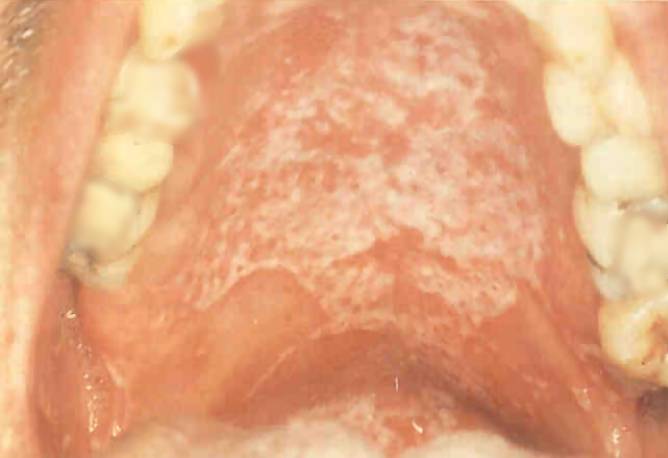

| Candidíase OralO palato do doente (acima)

e a língua (abaixo) mostram os sintomas da candidíase oral, uma infecção fúngica oportunista.